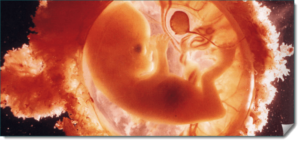

Прошло всего около семи недель с того момента, когда соединились две клетки, но за это время плод заметно подрос. На этом сроке размер плода составляет примерно 2,5-3 см, а весит плод около 2 граммов.

Внешне эмбрион выглядит похожим на гороховый стручок, но плод уже имеет головной мозг, у него имеется нервная и пищеварительная система. А сердечко плода, несмотря на свой крошечный размер, обеспечивает кровообращение маленького организма.

Плод на девятой неделе продолжает активно развиваться, буквально каждый день в организме плода формируются новые системы и органы. Это время, когда эмбрион «обретает» гипофиз, мозжечок, лимфатическую систему. Продолжают формироваться половые органы.

Нервная система продолжает совершенствоваться, так к концу девятой недели плод уже имеет спинномозговые и межпозвоночные нервы. С каждым днем эмбрион становится все больше похожим на человека. Плод к этому сроку уже имеет конечности, которые могут сгибаться. Начинают формироваться пальчики и ноготки.

Эмбрион не только меняется внешне, плод с каждым днем «приобретает» новые умения. Так, на девятой неделе плод уже может совершать глотательные движения и приобретает способность к мочеиспусканию. Выделение мочи проходит через пуповину, поэтому нагрузка на почки матери начинает возрастать.